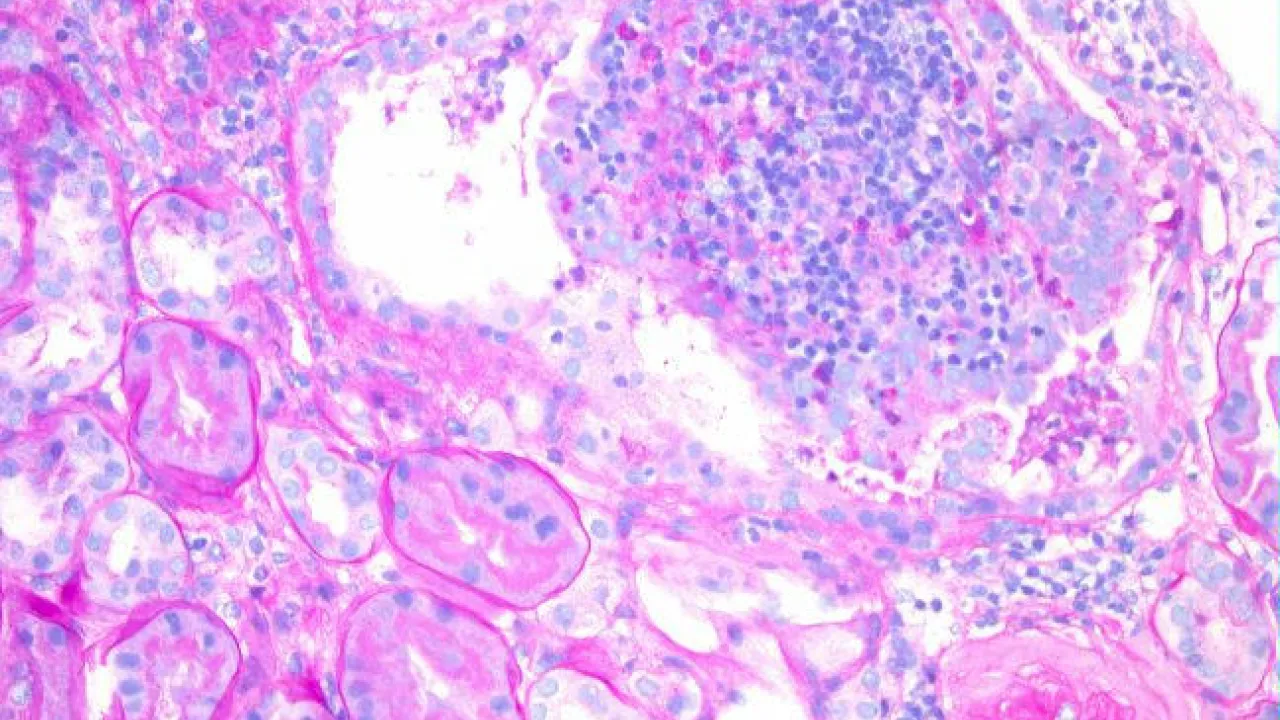

Kidney, Xanthogranulomatous pyelonephritis, PAS stain